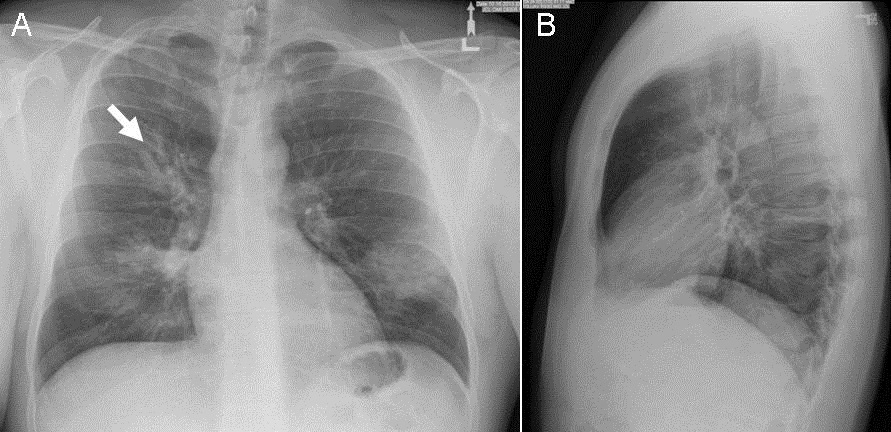

Finger in glove x ray sign

X ray - aspergilloma - opacity with a hole